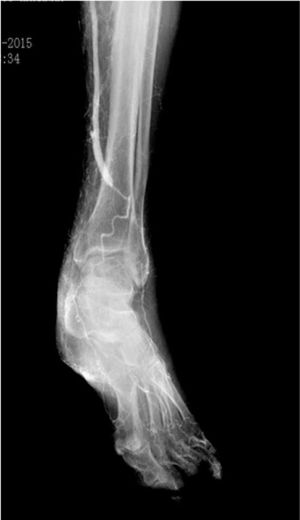

La fase siguiente de la planificación es la angiografía convencional diagnóstica, que realizamos sistemáticamente, excepto en pacientes con enfermedad renal crónica avanzada (depuración de creatinina <30ml/min). La inyección de contraste (80cc, 6ml/s, 600PSI de presión), se realiza mediante una punción femoral retrógrada con introductor 4F. Esta técnica permite el reclutamiento de todos los colaterales responsables de la irrigación de la pierna y del pie, desde la arteria femoral profunda, obteniendo así un gran detalle anatómico (fig. 2).

La calidad de la angiografía es crucial para la planificación de cualquier revascularización distal o ultradistal, con imágenes en 2 proyecciones y tiempos de exposición prolongados que permitan visualizar las arterias del pie. Los tiempos de exposición pueden alcanzar los 60s y, como tal, nos parece esencial la realización/supervisión de este examen por parte de un miembro del equipo con experiencia en este tipo de revascularización, con el fin de optimizar el uso de la radiación y disminuir la cantidad de contraste. En pacientes con contraindicación para la angiografía, se realiza la planificación basada exclusivamente en los hallazgos del eco-Doppler.